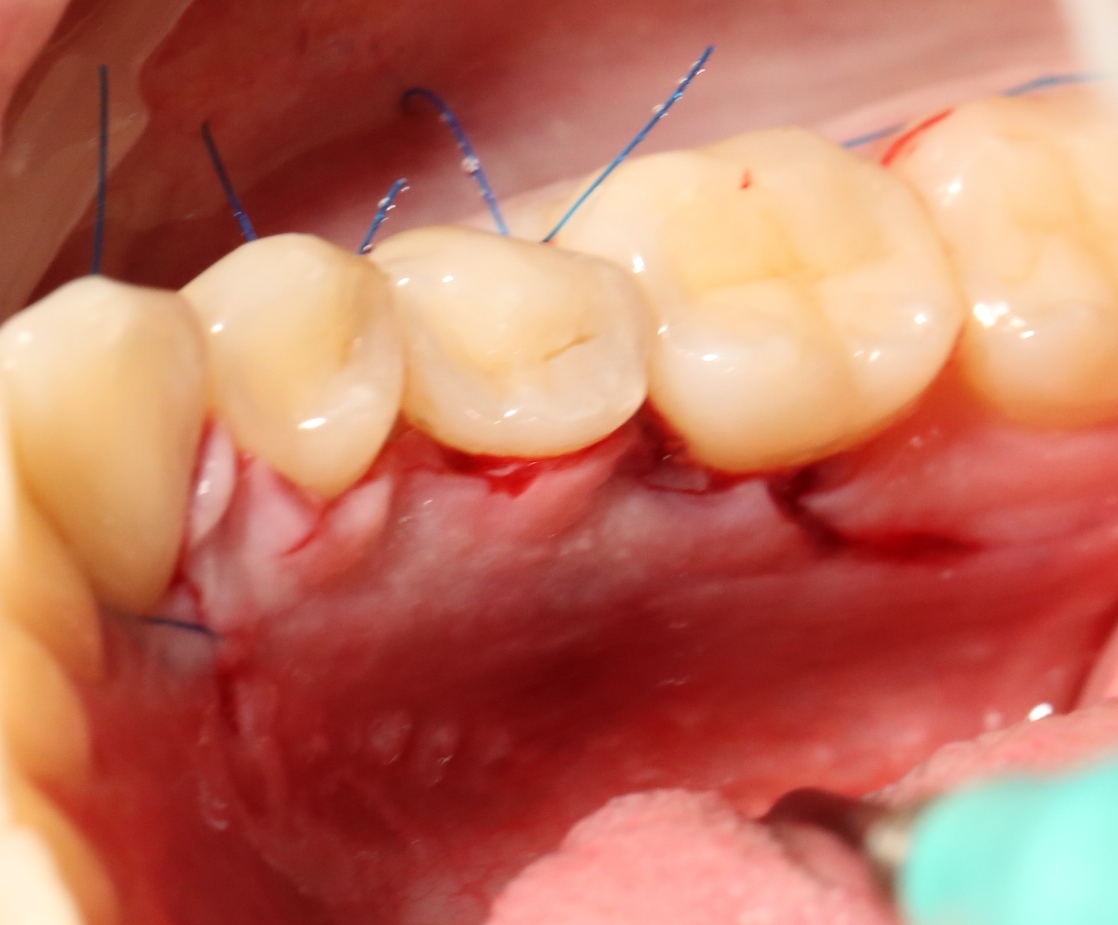

И накладываем швы.

Благодаря сделанному нами разрезу, мы можем вывести узелки на внешнюю сторону альвеолярного отростка, что будет удобнее и комфортнее для пациента:

Вот фотография послеоперационной раны через пару дней:

Так, друзья, выглядит нормальная послеоперационная рана. Со швами я угадал. Это, кстати, Prolene 5-0.